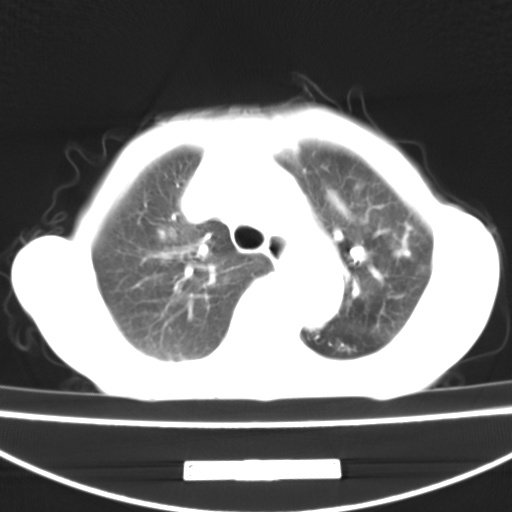

患者 女 67岁,反复咳嗽咳痰2年,加重伴喘及双下肢浮肿1月

诸大血管及f肺门血管增粗迂曲.左下肺多发薄壁空腔影.部分非也透亮度增高.薄曾扫描可区分肺气肿类型.考虑1.慢性支气管炎 2.左下肺支气管扩张 3.肺气肿 4 肺动脉高压5.是否有先心病病史

考虑1.慢性支气管炎 2.左下肺支气管扩张 3.肺气肿 4 肺动脉高压

慢支炎、肺气肿、双肺感染、左下囊状支扩。

慢支、肺气肿、肺动脉高压;左下肺囊状支扩并粘液栓形成。